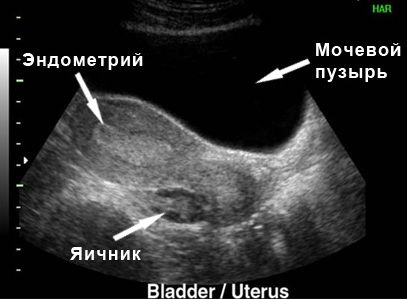

Для визначення вагітності на такому ранньому терміні використовуються спеціальні лабораторно-медичні дослідження. Серед них Доплерографія та УЗД. При цьому варто пам’ятати, що тонус матки в цей період – це сигнал відмови від гінекологічного огляду.

Застосування УЗД апарату та Доплера на такому короткому терміні допустимо при необхідності лікарської, але рекомендується на більш пізніх термінах. До того ж знімки на термін 2 тижні для більшості жінок є малоінформативними. При настанні вагітності фото містить тільки велике світле овальне пляма ендометрію, преобразующееся незабаром в повноцінний плід.